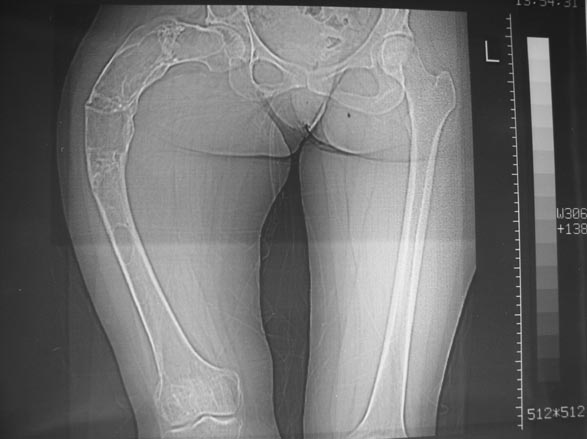

Моё мнение, что двойная остеотомия бедра с аппаратом Илизарова + Гексаподный механизм, или Тэйлора, В данной ситуации является методом выбора. Я очень извеняюсь за качество прилагаемых снимков, в которых я постарался отразить разницу междe одной и двумя остеотомиями бедра.

jo> отразить разницу межде одной и двумя остеотомиями бедра.

Скорее всего, второй уровень может оказаться нелишним лишь при переходе с аппарата на интрамедуллярный стержень. И его не поздно будет пересечь именно в момент введения гвоздя, если будет угроза перфорации стенки канала.

Если сделать фото больного после устранения деформации, вряд ли удастся догадаться, на скольких уровнях она устранялась.